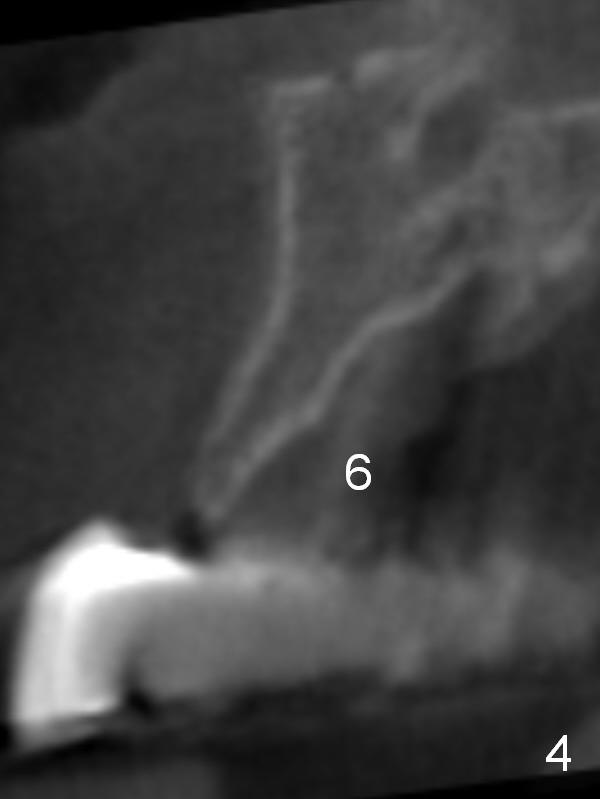

CT scan taken 10 days post immediate implant placement at #3, 4, and 10 shows that the edentulous area is narrow (Fig.1 (axial section), 2-6 (coronal sections; B: buccal)). In addition, the bone density is 100-200 Hounsfield units (Fig.2). Osteotomy should be underprep: 1.2 mm to the depth; 1.5 mm haft the depth. It appears that 2.5 or 3.0 mm 1-piece implants can be placed at #5,7 and 8 (Fig.3,5,6). Check buccopalatal trajectory after each step of osteotomy using surgical stent. Insert a 3 mm dummy implant tentatively. If it looks too wide for the ridge, use a 2.5 mm implant. If trajectory is off, use an angled one, especially at #7 (Fig.5).